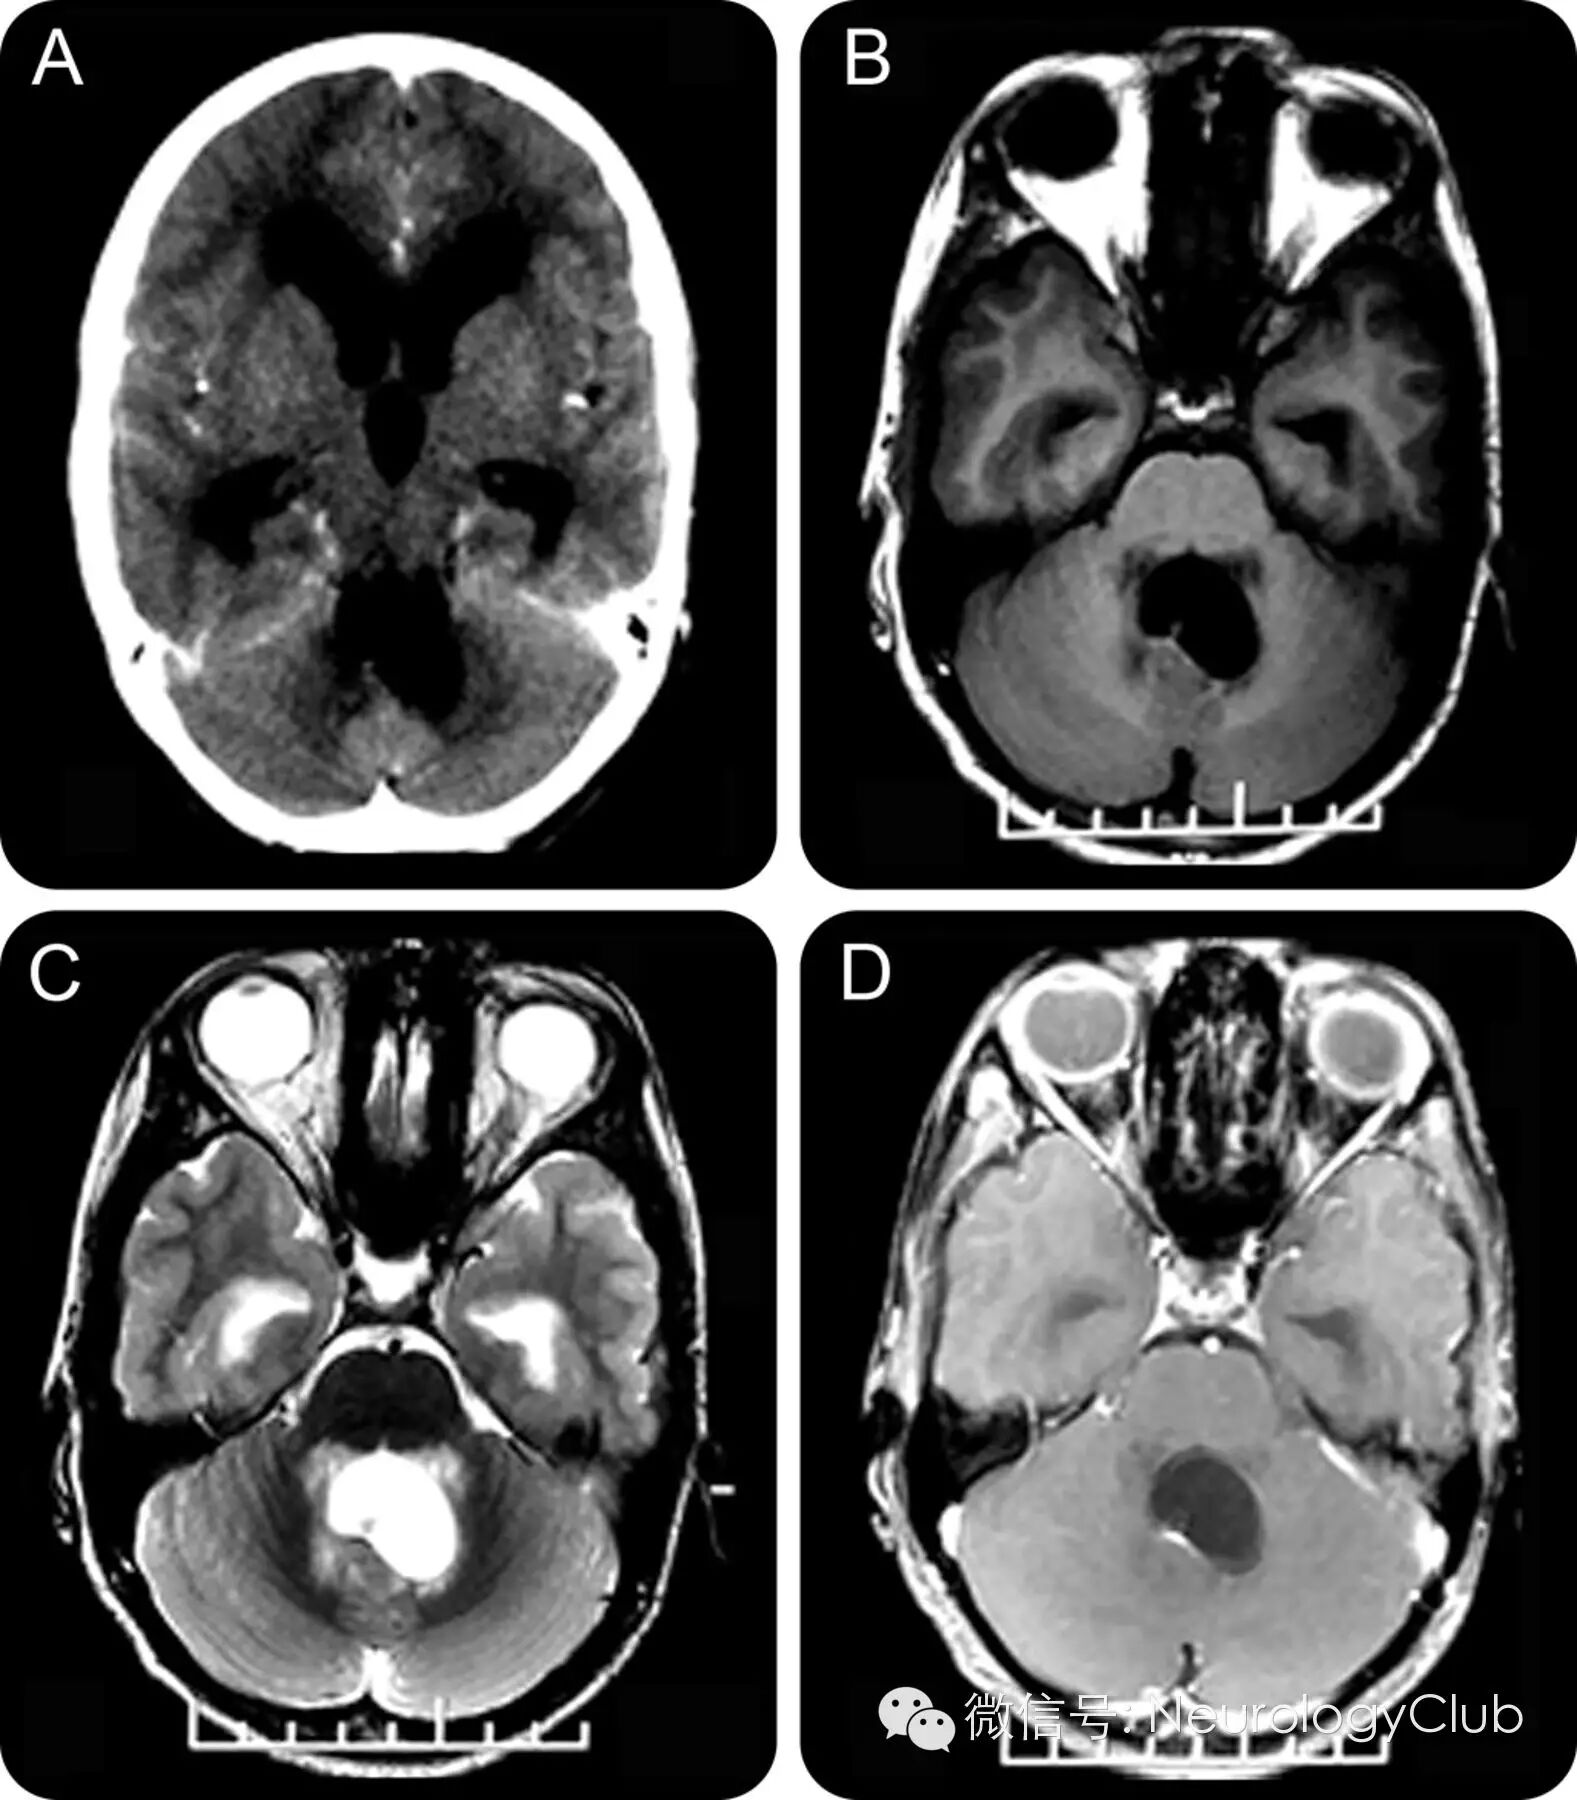

(图1 四脑室扩大,扭曲变形,可见结节 A:增强CT;B:T1WI;C:T2WI;D:增强MRI)

13岁男性,头痛1月,呕吐10天。查体提示左侧外直肌麻痹和视乳头水肿。头颅增强CT和MRI发现四脑室囊性病灶合并交通性脑积水(图1)。随后,患者行稳态构成干扰(constructive interference in steady state,CISS)序列检查,提示四脑室囊虫(图2)。